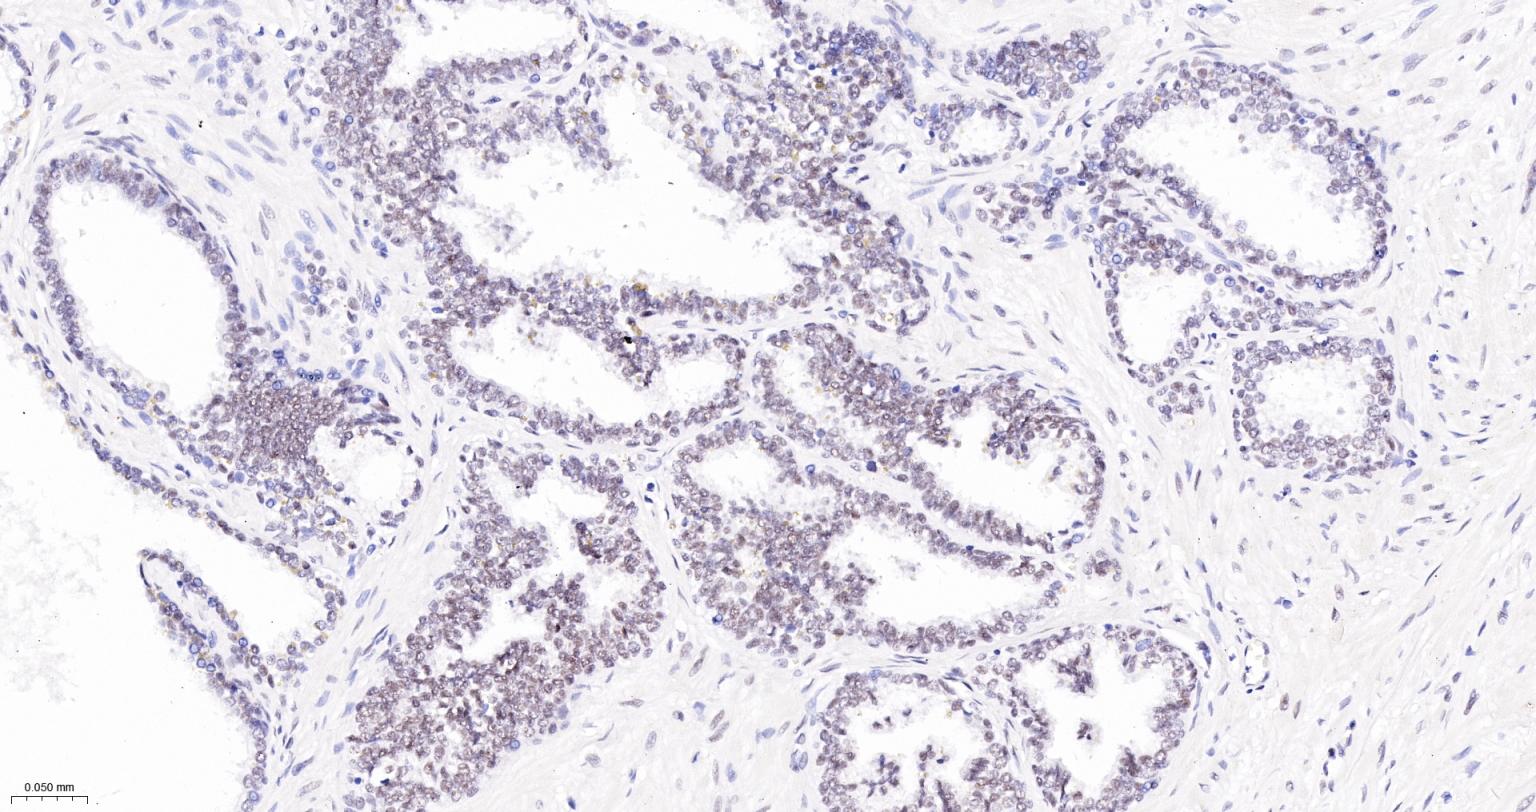

Paraformaldehyde-fixed, paraffin embedded Human Tonsil; Antigen retrieval by boiling in sodium citrate buffer (pH6.0) for 15 min; The section was incubated with USP39 Monoclonal Antibody, Unconjugated (bsm-63016R) at 1:200 overnight at 4°C, followed by conjugation to the bs-0295G-HRP and DAB (C-0010) staining.